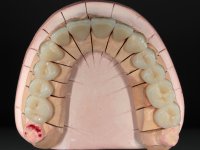

Paciente do sexo masculino, com 42 anos de idade, não fumador. Apresentava uma reabilitação metalo -cerâmica feita há mais de 10 anos com exposições radiculares e infiltrações. No maxilar superior apresentava uma coroa no 1.1,uma ponte de dois elementos no 2.1 e 2.2.e uma ponte de 4 elementos nos dentes 2.4,2.5,2.6 e 2.7 com o 2.6 como pôntico. Os dentes 1.6/1.5/1.4/1.3/1.2/1.1/2.1/2.2/2.3/2.4/2.5 e 2.7 apresentam tratamento endodôntico radical com o 2.4/2.5 e 2.7 a necessitarem de ser refeitos. No maxilar inferior apresentava uma ponte metalo-cerâmica de 4 elementos nos 4 incisivos e uma ponte de 3 elementos (3.3 e 3.4) com um dente supranumerário como pôntico. Os dentes 4.6/4.5 e 4.2 apresentavam tratamento endodôntico com o 4.2 a necessitar de ser refeito. Os dentes 4.3 e 4.4 apresentavam extensas cáries linguais com algum comprometimento mesial. As peças protéticas apresentavam-se infiltradas com exposição radicular associada. Apresentava uma D.V.O. diminuída e uma mordida cruzada lado direito. O paciente tinha uma satisfatória saúde periodontal e uma boa higiene oral.

Foi proposto ao paciente fazer uma reabilitação total com infraestruturas em zircónia revestidas a cerâmica. No maxilar superior, seriam realizadas 6 coroas (1.3/1.2/1.1/2.1/2.2/2.3), uma ponte de 3 elementos (1.4/1.5/1.6) e uma ponte de 4 elementos (2.4/2.5/2.6 e 2.7). No maxilar inferior, foram propostas 7 coroas (4.3/4.2/4.1/3.1/3.2/3.5 /3.6) e duas pontes (4.4//4.5/4.6) e (3.3/3.4#/3.4).O objetivo seria subir a D.V.O., descruzar a mordida do lado direito, eliminar as infiltrações e as exposições radiculares e reabilitar o paciente com estruturas protéticas com aspeto mais natural.

A primeira acção terapêutica foi tentar melhorar o tratamento endodôntico dos dentes (2.4/2.5/4.2)). A sua manutenção em boca seria condicionada pelo sucesso desta intervenção. Seguidamente foram feitas impressões em alginato e registo inter-maxilar em silicone para confeção em laboratório de uma ponte provisória em acrílico com reforço. O objetivo desta ponte provisória seria ensaiar o aumento da D.V.O. e descruzar a mordida do lado direito. Foi utilizado um monobloco de 13 dentes com o dente 2.6 com o pôntico. As coroas e as pontes foram removidas e os remanescentes coronários foram repreparados. A ponte provisória foi rebasada primeiramente com acrílico auto-polimerizável e de seguida com resina composta. Após 2 semanas de permanência em boca, foram feitas as impressões para confeção da ponte provisória inferior também realizada em laboratório. Especial cuidado foi colocado na remoção das coroas antigas, sendo feito primeiramente um corte axial que permitiu que fossem removidas de uma forma menos traumática. A temporização foi feita durante 8 semanas, permitindo que os tecidos gengivais estabilizassem posicionalmente. As impressões definitivas foram realizadas após afastamento gengival utilizando a técnica do fio único impregnado. Foi utilizada a técnica de dupla mistura com dupla viscosidade (putty soft e light).Simultaneamente foi realizada a recolha das relações inter-maxilares e o registo com arco facial. Foram confecçionados os modelos de trabalho e feita a sua correta montagem em articulador semi-ajustável. Em seguida foram feitas infra estruturas em zircónia que posteriormente foram revestidas por cerâmica. A prova de “biscoito” foi realizada em boca para avaliação estética e funcional sendo também avaliado o seu assentamento e ajuste. A reabilitação definitiva foi cimentada em boca utilizando um cimento de ionómero de vidro reforçado por resina.